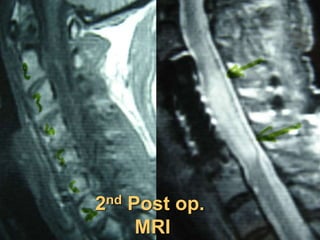

2nd Post op.

MRI